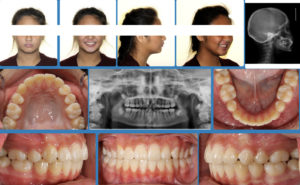

A 12 year old Asian female presents with a chief concern that “my teeth are crooked and I have a tooth stuck”